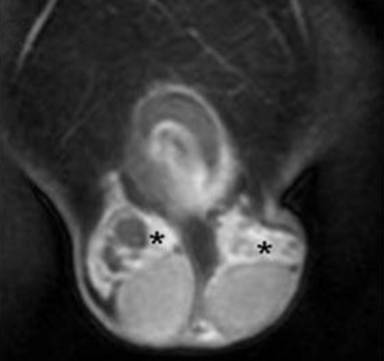

The scrotum MR imaging findings were: 1 (4.3%) fluid cystic lesion or cystadenoma (Figure 9) and none solid lesion.

Figure 9. Papillary cystadenoma of the epididymis. A 38-year-old man with VHL disease (the same case of Figure 8). Coronal 3D volumetric gradient-echo T1-weighted fat suppressed images after intravenous contrast medium administration during portal venous phase of contrastographic dynamic study. Bilateral complex cystic mass of epididymis with extratesticular site, fluid components, irregular septa inside the lesion and solid mural nodules which show enhancement after intravenous contrast medium administration during arterial phase (asterisks). Testicular resection was performed. Histological specimen showed the presence of bilateral papillary cystadenoma of the epididymis. |